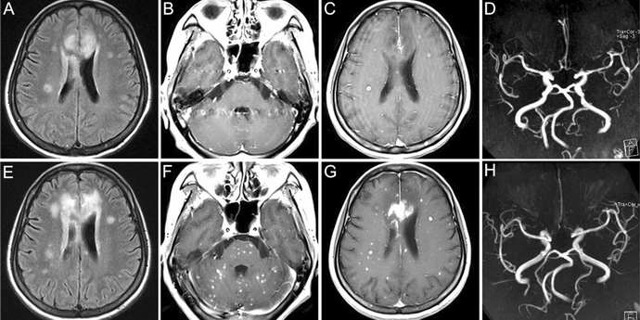

При развитии острой закупорки сосудов головного мозга используется МРТ или КТ головного мозга с целью визуализации развившегося инсульта.

- Магниторезонансная томография. Является полномасштабным анализом структуры мозговых тканей и сосудов. Метод исследования определяет отклонения от нормы, которые становятся причиной аномальных изменений.

МРТ сосудов головного мозга позволит доктору получить полное представление о состоянии тканей мозга и своевременно принять меры, исключив летальный исход или наступление постоянной инвалидности.